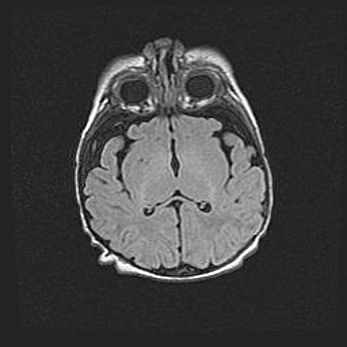

Неполная лизэнцефалия (пахигирия). Открытая гидроцефалия.

Возраст: 17 дней

Вес: 3110 г

Пол: мужской

Окружность головы: 33,5 см

Срок гестации: 35-36 недель

Лизэнцефалия—недоразвитие корковой пластинки и мозговых извилин в результате нарушения миграции нейронов коры. Поверхность мозговых полушарий гладкая. Микроскопически выявляется отсутствие нормальных слоев коры и скопление групп нейронов в подкорковом белом веществе.

Пахигирия—уменьшение числа вторичных извилин. В пораженном полушарии нервные клетки образуют толстый недифференцированный слой с неправильно расположенными нервными волокнами и группами гетеротопных клеток. Нервные клетки незрелые. Белое вещество истончено. При этом нередко аномально развит корково-спинномозговой путь.